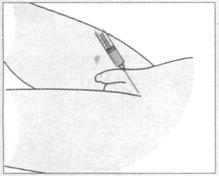

●佩戴无菌手套,确认桡动脉的走行后,选取穿刺点,右手进针,同时左手的食指和中指沿桡动脉走行方向挤压血管(图84)。持续进针,直至动脉血依靠自身的压力充满血气管。

图84 从桡动脉抽取血气标本